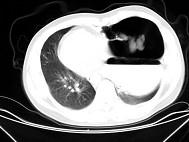

女,6岁,胸闷,咳嗽,胸部CT如图,最可能的诊断为 ( )A.畸胎瘤B.右侧液气胸C.右肺肺大疱D.右侧脓胸E.支气管囊肿并感染